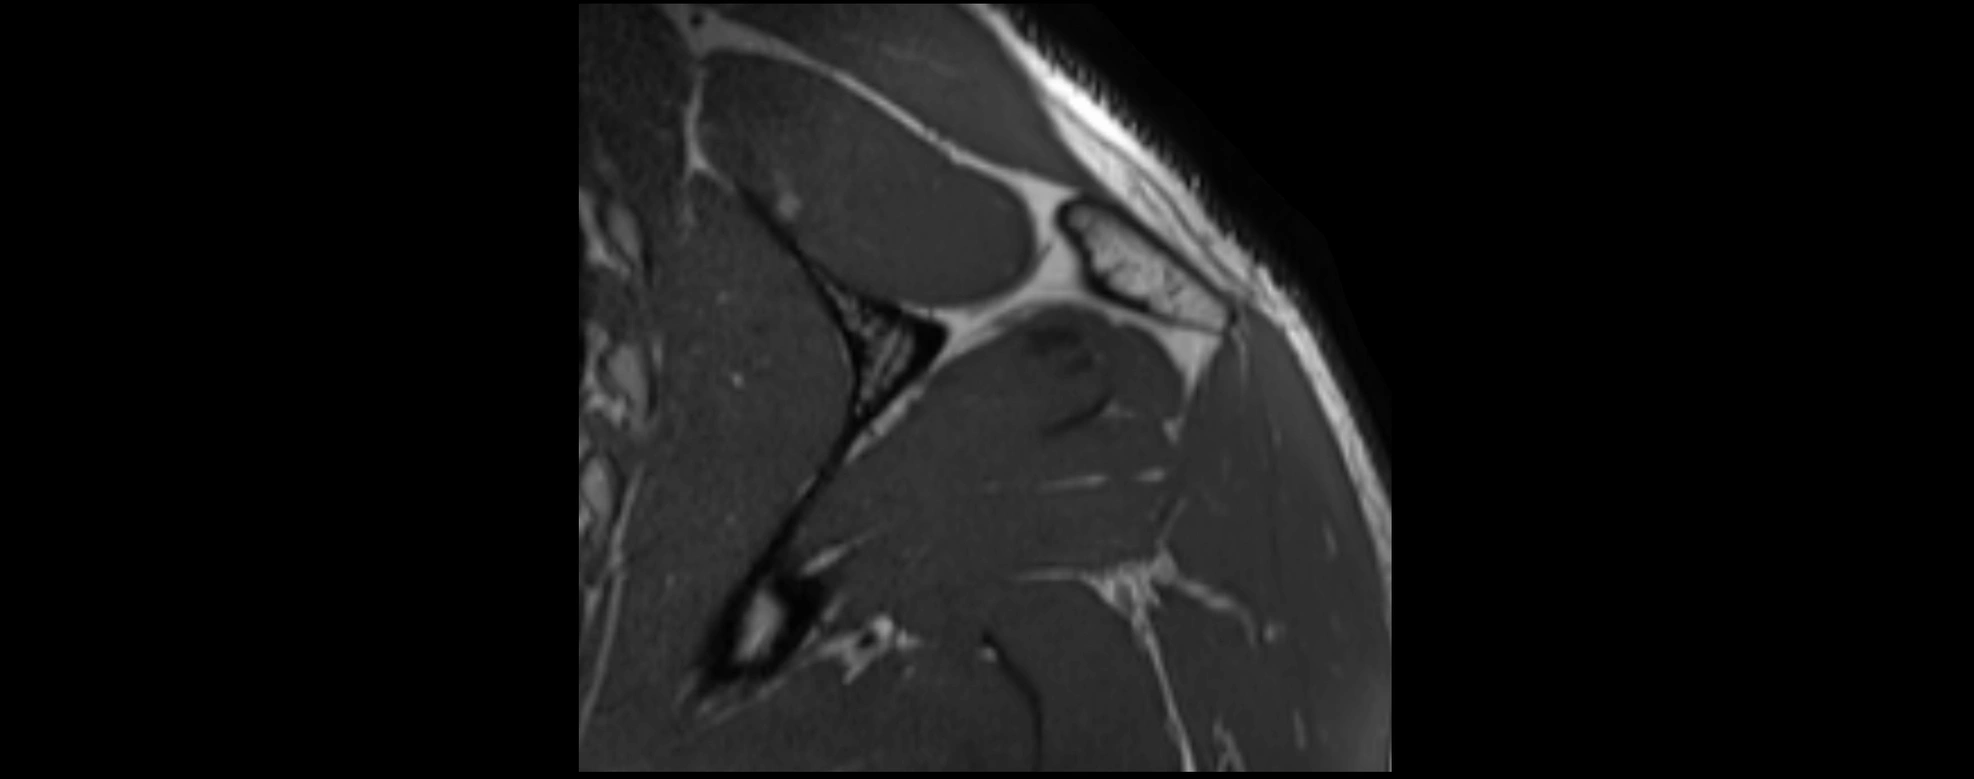

CT image

image